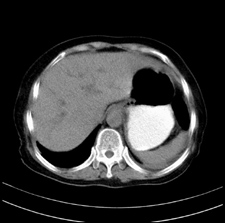

患者,女,75岁。腹痛,体黄5日,膝胸位时腹痛缓解。肝功能明日出来。彩超提示胆总管占位,未见血流信号。心电图提示s-t段改变。患者体质较弱,未能增强。

胆总管上段,腔内有软组织密度影 ,ct值36-44hu。大家看有没有胆管癌的可能。

典型胆总管多发结石;增强扫描前后ct值是否发生改变是鉴别结石与占位的依据。